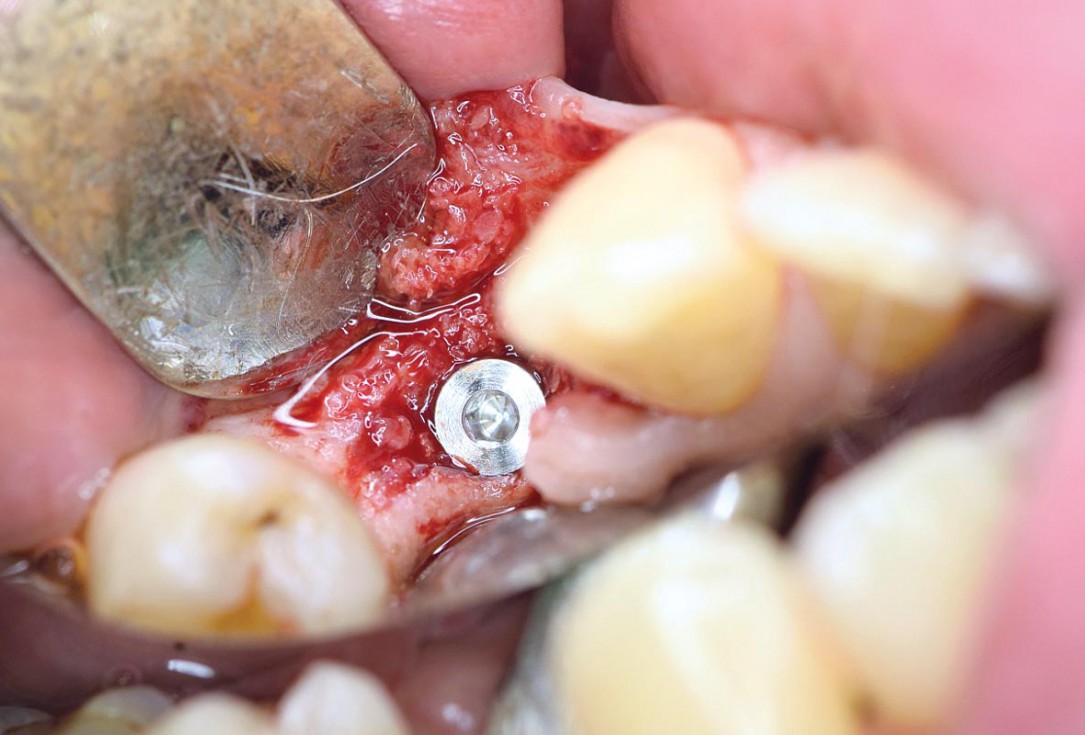

Posterior socket preservation using maxgraft® and permamem® - Dr. C. Landsberg

Implant placed in the deficient site. permamem® in place for covering.